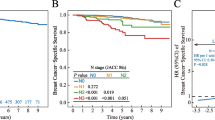

Of 285 patients with tumor-involved SLNs, 101 (35.4%) were found to have NSLN metastases, with tumor metastases to two or more NSLNs in the majority of cases (median number of positive NSLNs 2; mean 3.5; range 1–19) (Additional file 2). By univariate analyses, 8 variables were highly predictive of NSLN status: tumor size (in cm), tumor size by AJCC T classification, tumor grade, ER status, PR status, angiolymphatic invasion, size of SLN metastasis, and whether the nodal metastasis was identified by H&E or IHC (Table 1). Of patients whose SLN was identified by H&E, 45% had NSLN metastases, whereas only 4.6% of patients whose SLN was identified by IHC had NSLN metastases (p < 0.001). Size of SLN metastasis and staining method for metastasis identification are highly correlated (p = 0.02, by χ2 testing) and therefore are not independent predictors of NSLN status. Thus, staining method for identifying tumor-involvement was not included in the multivariate analysis shown in Table 1. By multivariate analysis, tumor size, angiolymphatic invasion, and size of SLN metastasis remained significantly predictive of NSLN status (p < 0.001 by unconditional testing). Of the 285 patients with SLN metastases, NSLN metastases were found in 25% of patients with T1 tumors; in 46% with T2 tumors; and in 60% with T3 tumors (Figure 1A). When angiolymphatic invasion was present, there was a 3.9-fold increase in NSLN metastases (74% vs. 19%, Figure 1B). Among patients with isolated tumor cells or clusters within the SLN, 4.7% had NSLN metastasis; whereas 42% of patients with micrometastasis and 71% with macrometastasis had NSLN involvement (Figure 1C and Table 1).

Table 3 compares the sensitivities, specificities, and predictive accuracies of our three models, RP-ROC, boosted CART, and MLR, all computed with 10-fold cross validation [26]. As different models require different information, we evaluated models for the entire group (n = 285, only possible for CART) and subsets that contained complete information on angiolymphatic invasion (n = 213), and alternatively, on angiolymphatic invasion and ER status (n = 171). Cross-validated sensitivities/specificities of the three technologies for the group with known angiolymphatic invasion status (n = 213) were 79%/76% for RP-ROC, 88%/71% for boosted CART, and 78%/86% for MLR. Cross-validated specificity of boosted CART when inferred for the entire dataset (n = 285) was lower than when calculated using known values for angiolymphatic invasion (n = 213), suggesting that angiolymphatic invasion is informative in our dataset. This is supported by the continued selection of angiolymphatic invasion in CART modeling when patients have known angiolymphatic invasion status (n = 213) and known angiolymphatic status and ER status (n = 171) (Additional files 4 and 5, respectively). Overall diagnostic accuracy, based on areas under the ROC curve [34] (AUC), for predicting NSLN metastasis among patients in our database was greatest by MLR (83% and 85%) for the subsets of patients for whom the computation was possible (n = 213 and n = 171, respectively). Further, we applied the Nomogram to our SLN-positive patients who had complete data available for entry of its eight variables (n = 171, all patients with known angiolymphatic invasion status and ER status). Figure 3 shows a graph of the ROC curve that devolves from our MLR using our two composite variables (n = 213) and the ROC curve that devolves from the Nomogram (n = 171). Because much preprocessing has gone into our computations, p-values we might report (regarding a null hypothesis that the "true" areas under the curves are equal) would be suspect. However, the diagnostic accuracy or area under the curve (AUC) for our MLR is 83% (95% confidence interval 0.81–0.86), and the AUC for the Nomogram is 77% (95% confidence interval 0.73–0.81). When we use the same patients as used in the Nomogram for the MLR calculation (n = 171), our model achieves cross-validated AUC of 85% (95% confidence interval 0.81–0.89). Given that only three variables were used to calculate our MLR, the difference is noteworthy.

ROC curves for MLR informed by CART calculation in blue, AUC = 0.83, and Nomogram in green, AUC = 0.77, when applied to the Bay Area SLN Database. Note that MLR informed by CART calculation was done for larger group of patients (n = 213). When it was performed for the same patient group as the Nomogram (n = 171), AUC increased to 0.85.

Finally, the MLR and Nomogram were applied to a database of 77 patients who received ALND for positive SLNs at Northwestern University (Additional file 6). The SLN metastases in this dataset were identified by H&E stain without IHC. Among the 77 SLN positive patients, 61% had T1 tumors, 36% had T2 tumors, and 2.6% had T3 tumors. Angiolymphatic invasion was present in 68% of patients' tumors, and the SLN metastases in the Northwestern dataset were predominantly of large tumor burden with 56% having macrometastasis. NSLN metastases were present in 24 patients (31%). This is in contrast to the Bay Area SLN dataset with 55% T1 tumors, 38% T2 tumors, and 7% T3 tumors; 45% with angiolymphatic invasion (when angiolymphatic invasion status was known); 7% with macrometastasis; and 35% NSLN metastases (Table 1 and Figure 1). Although the Northwestern tumors were somewhat smaller, the higher percentage of angiolymphatic invasion and SLN macrometastases suggest more biologically aggressive disease in their dataset, yet they had a slightly lower percentage of NSLN metastasis.

Both the MLR model and the Nomogram performed less well when applied to the Northwestern dataset; however, the MLR model was supported with an AUC of 77% (95% confidence interval 0.67–0.80). This is superior to the performance of the Nomogram among this population, 62% (95% confidence interval 0.55–0.68) (Figure 4).